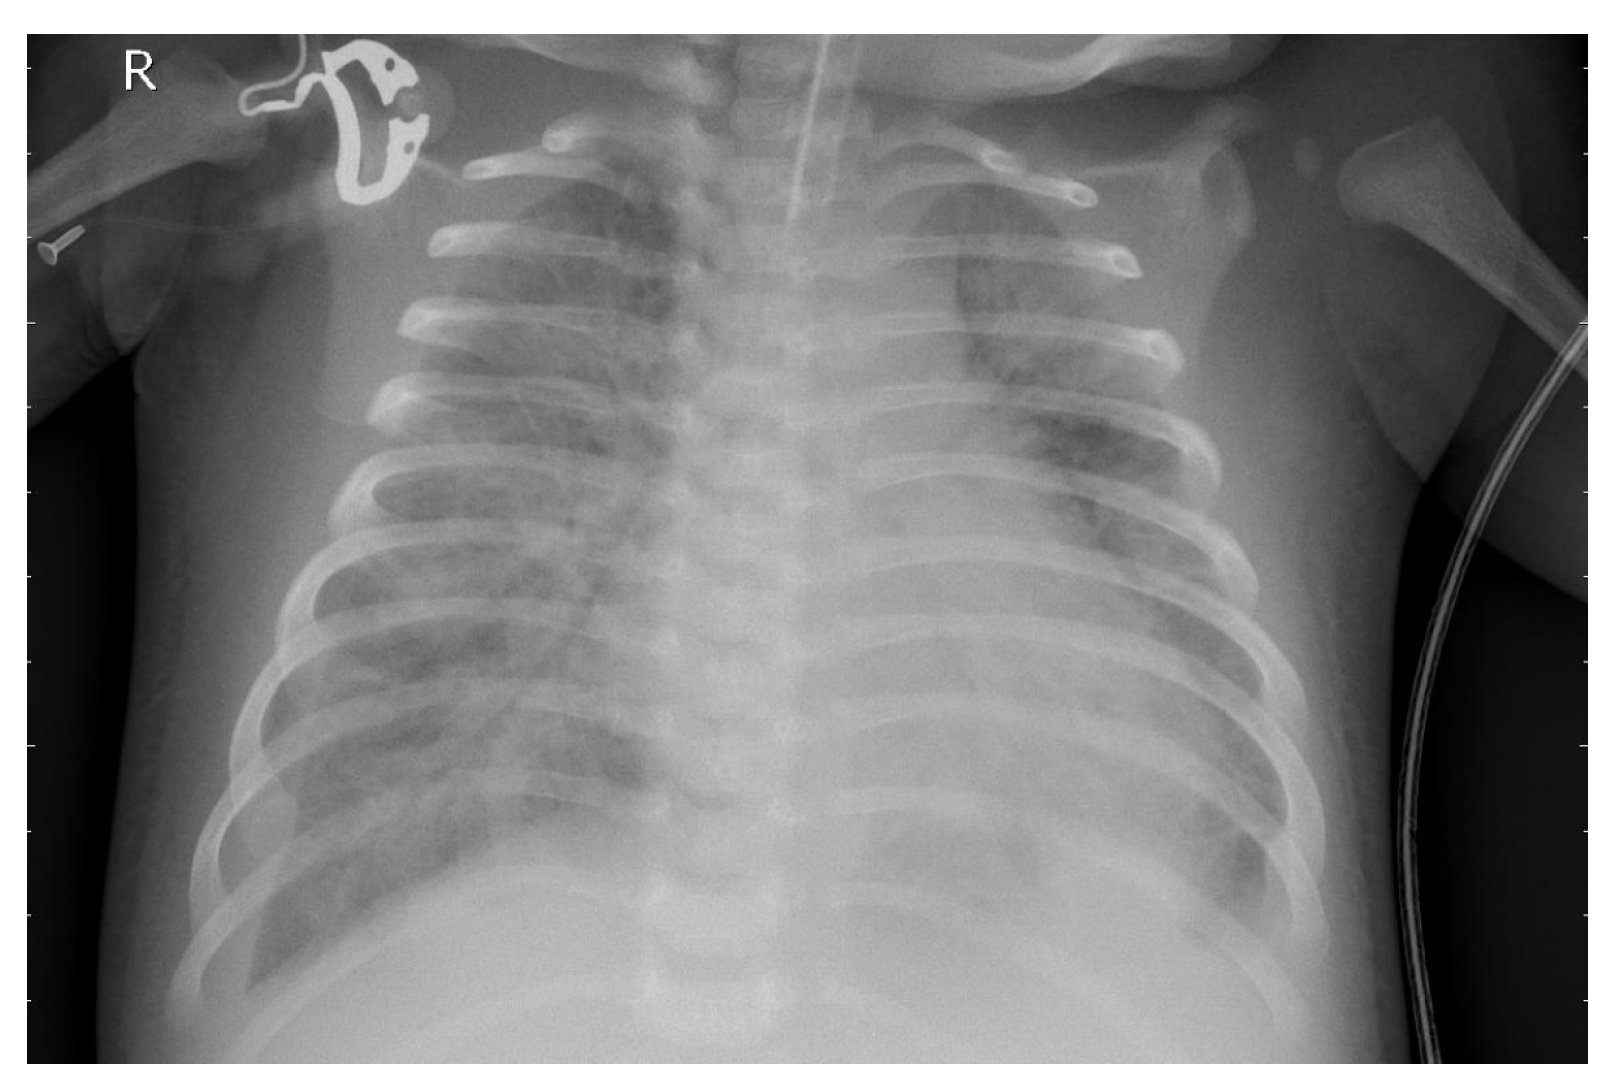

3.1. Dataset

3.8. Explainability Analysis